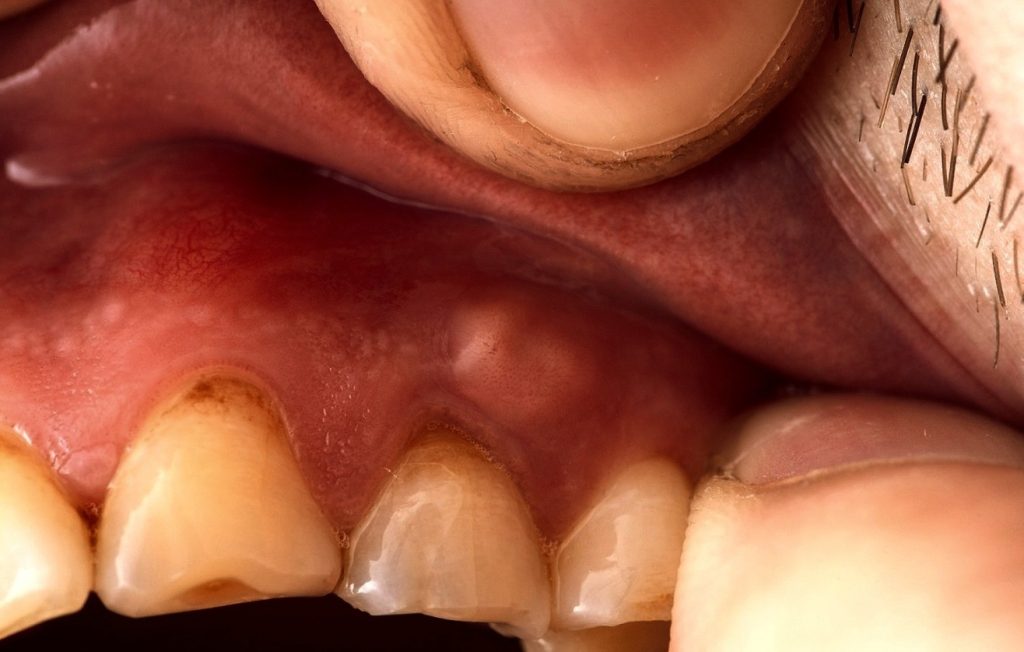

Diş apsesi, diş kökünün ucunda veya diş etinde oluşan, içi iltihap ve ölü hücrelerle dolu bir keseciktir. Bu durum, genellikle bir bakteriyel enfeksiyonun sonucudur ve vücudun enfeksiyonla savaşmak için oluşturduğu bir savunma mekanizmasıdır.

Apse, dişin içindeki yumuşak dokudan (pulpa) başlayarak, diş kökünün ucuna veya çevresindeki kemiğe kadar ilerleyebilir.

Diş apseleri oldukça ağrılı olabilir ve tedavi edilmezlerse ciddi sağlık sorunlarına yol açabilirler. Enfeksiyon, çene kemiğine, yakın dişlere ve hatta vücudun diğer bölgelerine yayılma potansiyeline sahiptir. Bu nedenle, diş apsesi fark edildiğinde hızlı bir şekilde tedavi edilmesi hayati önem taşır.

- Diş Etinde Kırmızılık ve Şişlik: Özellikle periodontal apsede, diş eti kırmızı, şiş ve hassas olabilir.

- Periodontal Apse: Diş eti dokusunda, genellikle diş kökünün yanında oluşur. Çoğunlukla ileri periodontal hastalıkların bir sonucudur. Bu tür apse, diş eti ve diş arasındaki ceplerde biriken bakterilerin neden olduğu enfeksiyon sonucu oluşur.

- Gingival Apse: Diş eti yüzeyinde oluşan, genellikle daha yüzeysel bir apsedir. Çoğunlukla diş etine batan yabancı bir cisim (örneğin, bir yemek parçası) nedeniyle ortaya çıkar. Bu tür apse, diğerlerine göre daha az yaygındır ve genellikle daha kolay tedavi edilir.